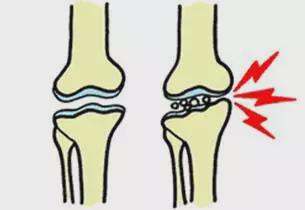

风湿病是以累及肌肉、肌腱、滑膜、滑囊、筋膜、韧带、骨、关节等系统,以疼痛为主要临床表现的一大类疾病的总称。好发人群不限年龄,不限性别。目前至少包括伴发关节炎或有关肌肉骨骼综合征的100多种疾病。由于大多数风湿病的病因尚未能完全阐明,而且自身免疫的复杂病理机制决定了这类疾病为公认的“难治性顽疾”。不少病种的病程冗长、病情迁延、反复发作、缠绵难愈,甚至最后导致肢体残废、脏器功能丧失和死亡,严重危害病人的身心健康。

二、关节痛

关节痛是风湿病的最常见症状。急性关节痛是急性关节炎的主要症状,局部皮肤还可出现肿胀、潮红、皮温升高和活动受限等。慢性关节病变常迁延数月甚至数年,临床主要表现为关节畸形和不同程度的关节功能障碍,部分还可致残。家长应该注意孩子起病缓急,关节病变是单发还是多发,病程长短,关节痛是持续性还是间隙性,发病与季节的关系等。